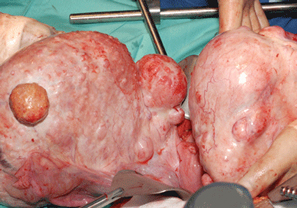

Liver Cancer

The most typical form of primary liver cancer is hepatocellular carcinoma (HCC). Unlike tumors that metastasis to the liver from other organs primary liver cancer refers to cancer...

Uterine Fibroids

Smooth muscle cells and fibrous connective tissue combine to form tumors known as fibroids, which form in the uterus. According to estimates, 70 to 80 percent of women may experience fibroid...